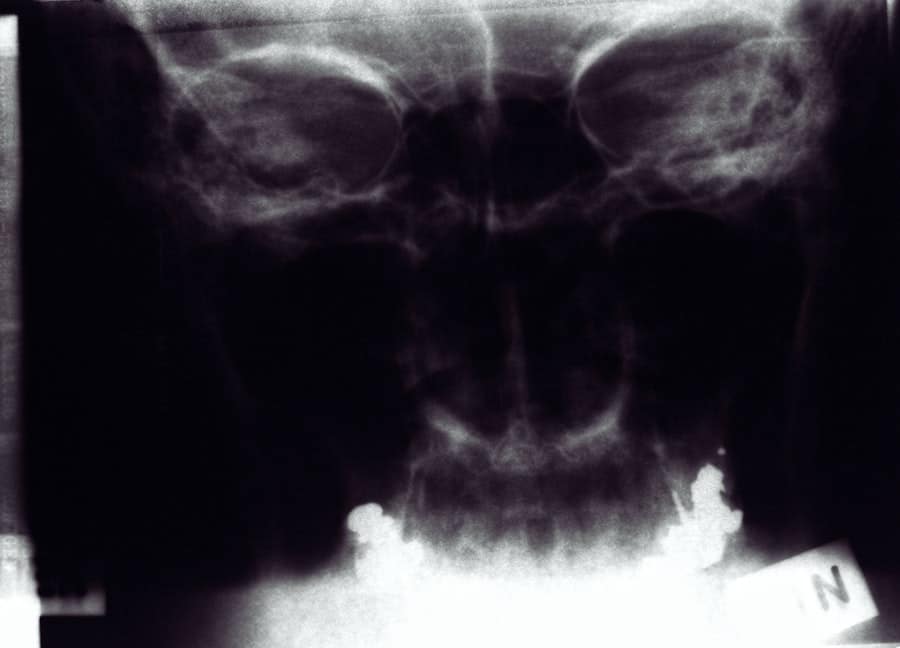

Several factors can influence the overall cost of rhinoplasty, and understanding these can help you better prepare for your financial commitment. One of the primary factors is the complexity of your specific case. If you require extensive reshaping or if there are functional issues that need to be addressed, such as a deviated septum, the procedure may be more intricate and thus more expensive.

Insurance coverage for rhinoplasty can be complex and varies depending on individual policies and circumstances. If your rhinoplasty is deemed medically necessary—such as correcting breathing issues caused by structural abnormalities—your insurance may cover part or all of the costs associated with the procedure. However, if you are seeking rhinoplasty solely for cosmetic reasons, it’s unlikely that insurance will provide any coverage.